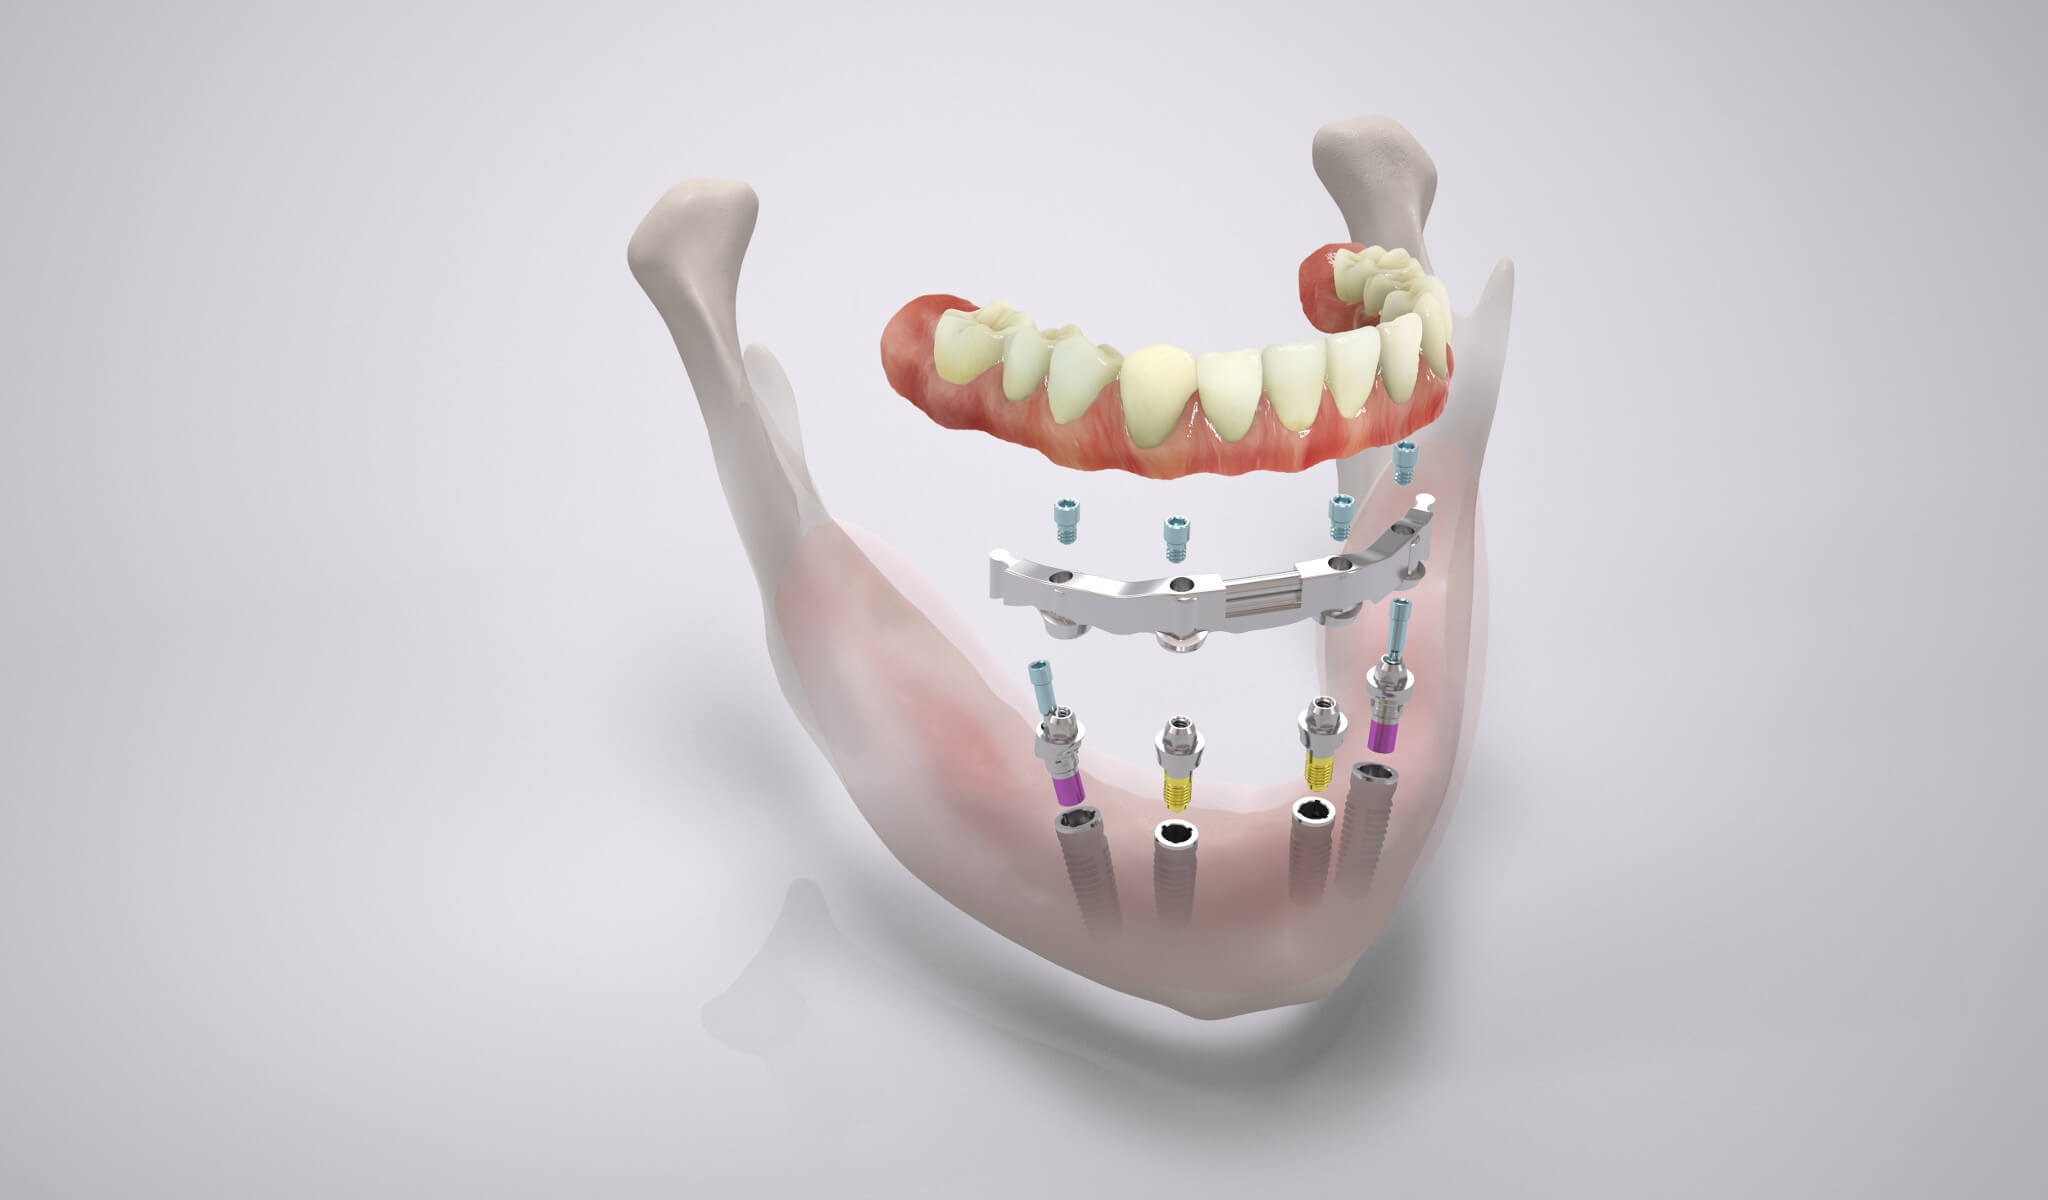

Schöne, feste dritte Zähne auf nur 4 oder 6 Implantaten an einem einzigen Tag und das am liebsten ohne vorherigen Knochenaufbau? Das wünschen sich viele Patienten der Praxisklinik Herne. Die erfreuliche Nachricht: Dank des All-on-4 ® / All-on-6 ® – Behandlungskonzeptes rückt die Erfüllung dieses Traumes in greifbare Nähe. Schnell, sicher und kostengünstiger als die meisten anderen Versorgungen auf Implantaten.

All-on-four Zahnbrücke - Malo Konzept - Schema

Alternativ lassen sich abnehmbare Prothesen auf einem Steg verankern. Hierzu werden die vier Comfour-Implantate mit einem Steg verblockt. Die Gegenstücke der Stege bilden die in die Prothese werden eingearbeiteten „Stegreiter“, die beim Einsetzen der Zahnprothese auf den Stegen der Implantate einrasten. Durch die Stege entsteht eine sehr starke Verblockung der Zahnimplantate, sodass diese sofort belastet werden können. Zahnersatz auf Stegen kann bei schlechteren Knochenverhältnissen sinnvoll sein.

All-on-four-Prothese auf Stegversorgung - Schema

All-on-four: Brücke auf vier Zahnimplantaten

All on four mit einer verschraubten Brücke (Malo-Konzept)

Können Zahnimplantate in ausreichender Länge/Größe in den Kiefer implantiert werden, besteht die Möglichkeit, die vier Implantate mit einer festsitzenden Brücke zu verschrauben.